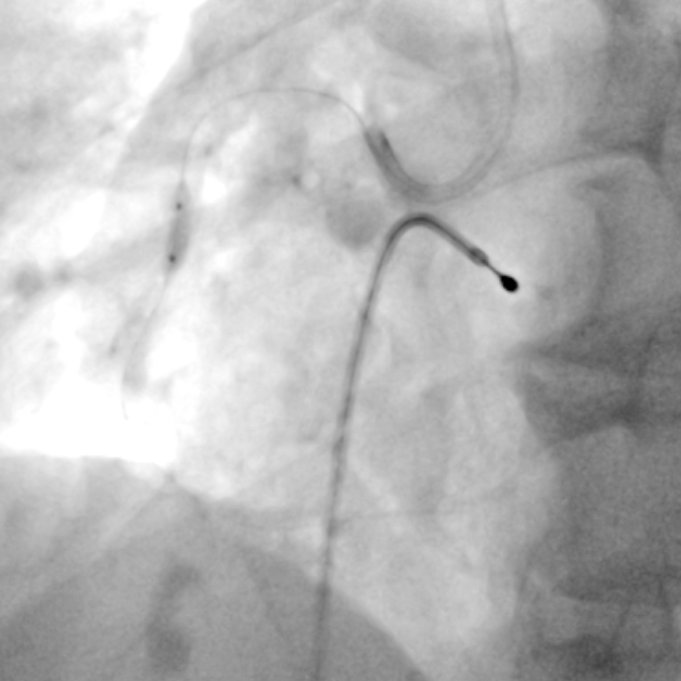

PCI过程-冲击波球囊PTCA

沿导丝送3.0×12mmGennWave冲击波球囊至RCA严重钙化病变处,充盈1:1比例造影剂盐水,以4atm低压扩张,每周期给予10秒、每秒1次血管内冲击波治疗后扩张至6atm,共进行8周期血管内冲击波治疗。